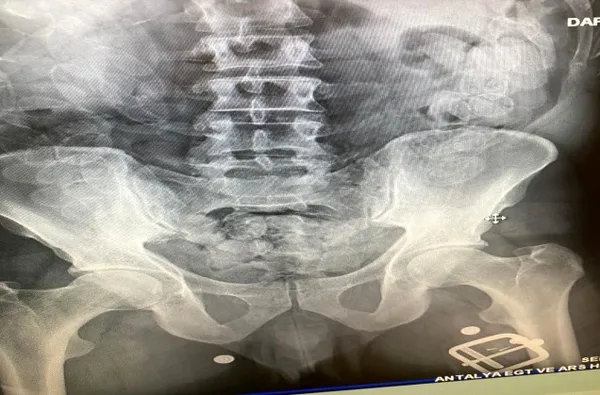

Antalya Emniyet Müdürlüğü, Narkotik Suçlarla Mücadele Şube Müdürlüğü Hudut Kapıları Büro Amirliği ekipleri havalimanını kullanarak diğer illerden veya ülkelerden uyuşturucu madde nakli yapan kişi ve gruplara yönelik yürüttüğü çalışmada, Fas'tan Antalya Havalimanına gelen uçuktan inen Hassane L.'nin durumundan şüphelendi. Gözaltına alınan 43 yaşındaki Hassane L., hastaneye götürülerek göğüs filmi çektirildi.

Zanlının yaptırılan iç beden muayenesinde 100 adet kapsül halinde 1 kilo 100 gram macun esrar maddesi ele geçirildi. Midesindeki uyuşturucu kapsülleriyle 8 saat yolculuk yapan Hassane L., Antalya Cumhuriyet Başsavcılığı talimatıyla "Uyuşturucu veya Uyarıcı Madde Ticareti Yapma veya Sağlama" suçundan ifadesi alındıktan sonra adliyeye sevk edildi.